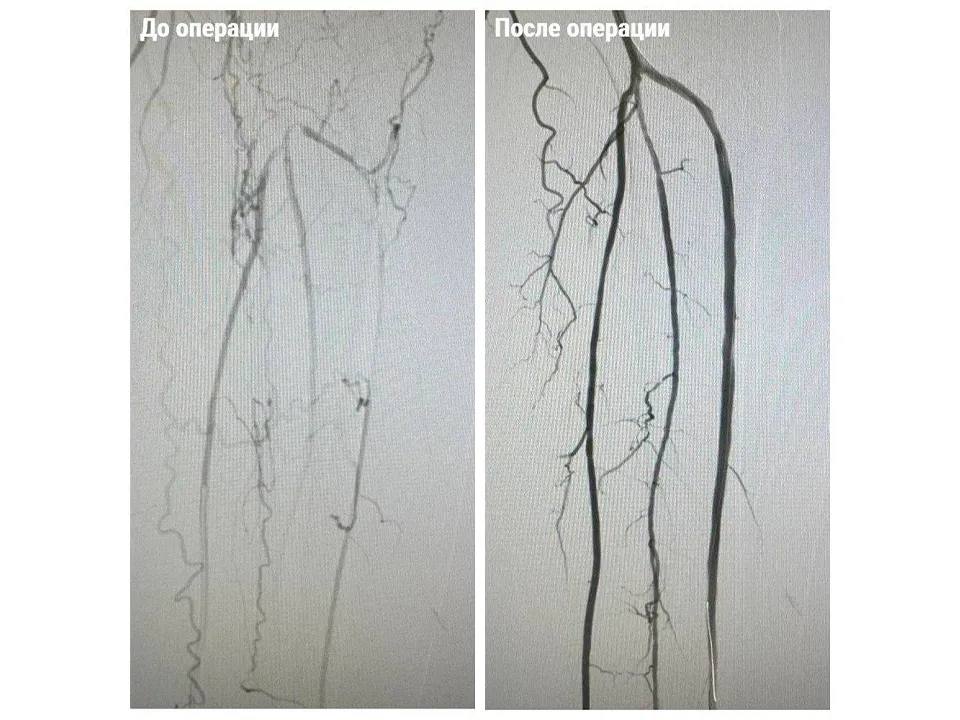

Мужчина поступил в Королевскую больницу с жалобами на онемение и потерю чувствительности в левой ноге, а также с трудом преодолевал расстояния более 20 метров. Диагностика выявила критическую ситуацию — закупорку поверхностной бедренной, подколенной и тибиальной артерий. Такая патология без своевременного вмешательства неизбежно приводит к ампутации конечности.

Врачи приняли решение о проведении двухэтапной операции, которая объединила в себе открытое хирургическое вмешательство и передовые рентгенэндоваскулярные технологии.